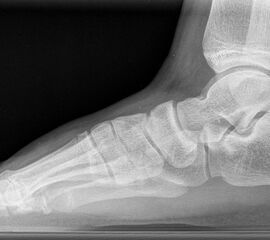

Standard ist die belastete Röntgenaufnahme des Fußes dorso-plantar und seitlich. Günstig ist eine Röhrenkippung von 10°-20°, um die Gelenke der Lisfranc-Linie einsehen zu können.

Ergänzend kann eine Schrägaufnahme hilfreich sein. Bei Metatarsalgien oder Pathologien der Sesambeine liefert die Sprinteraufnahme zusätzliche Informationen. Bei einer Pes planovalgus Fehlstellung wird ergänzend ein Saltzman view durchgeführt.

• Elevation/ Plantarisierung I. Strahl

• Pes metatarsus adductus